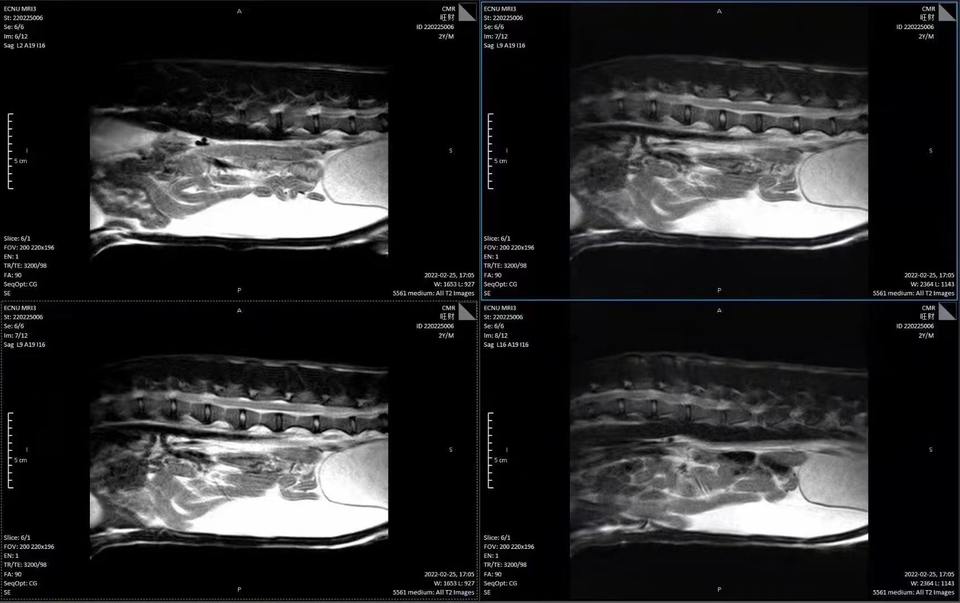

Nombre del producto::MRI para mascotas

Función::Diagnóstico de imágenes médicas veterinarias